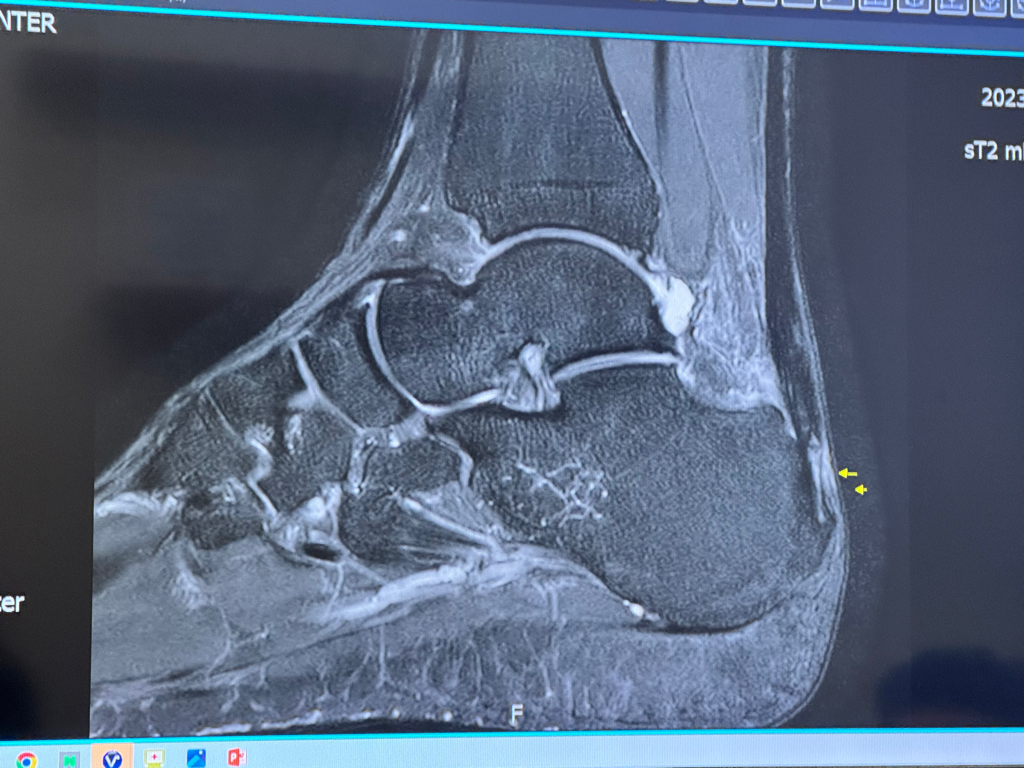

아킬레스건 자연적으로 회복 가능성 있을까요?

아킬레스건 부착 쪽에 일부 파열이 있는데 30-40프로 정도 손상이라고 합니다

해당발 뒷꿈치 위가 아무래도 다른발보다 살짝 볼록 튀어나왔고 온찜질 관리하니 조금씩 가라 앉는것 같습니다

• 유감스럽지만 좋아질 것이다 아니다 구체적으로 딱 판단하기는 어렵습니다. 완전한 파열이 된 것이 아니라 30-40프로 정도 손상이라면 비수술적 치료를 통해서 회복이 될 수 있을 가능성이 있긴 합니다만 실제로 어떻게 될지는 경과를 지켜보아야 하며 미리 확실히 알 수 없습니다.